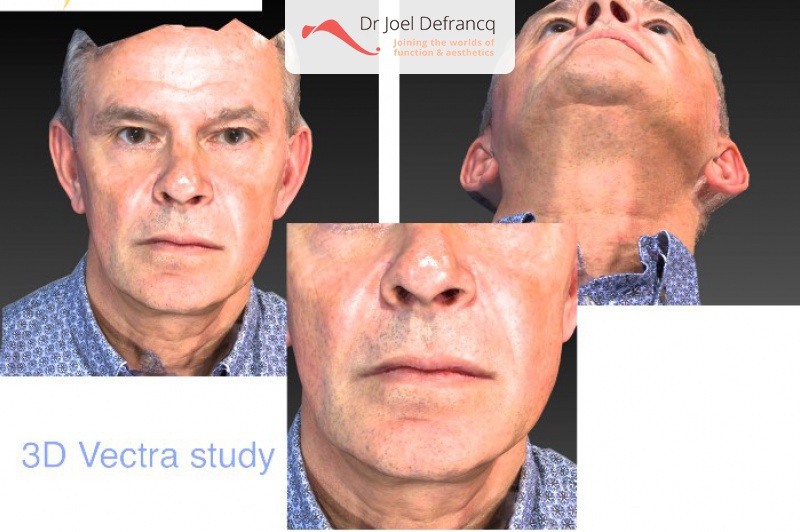

Diagnose van het gezicht

- Te kleine bovenkaak

- Te korte bovenkaak